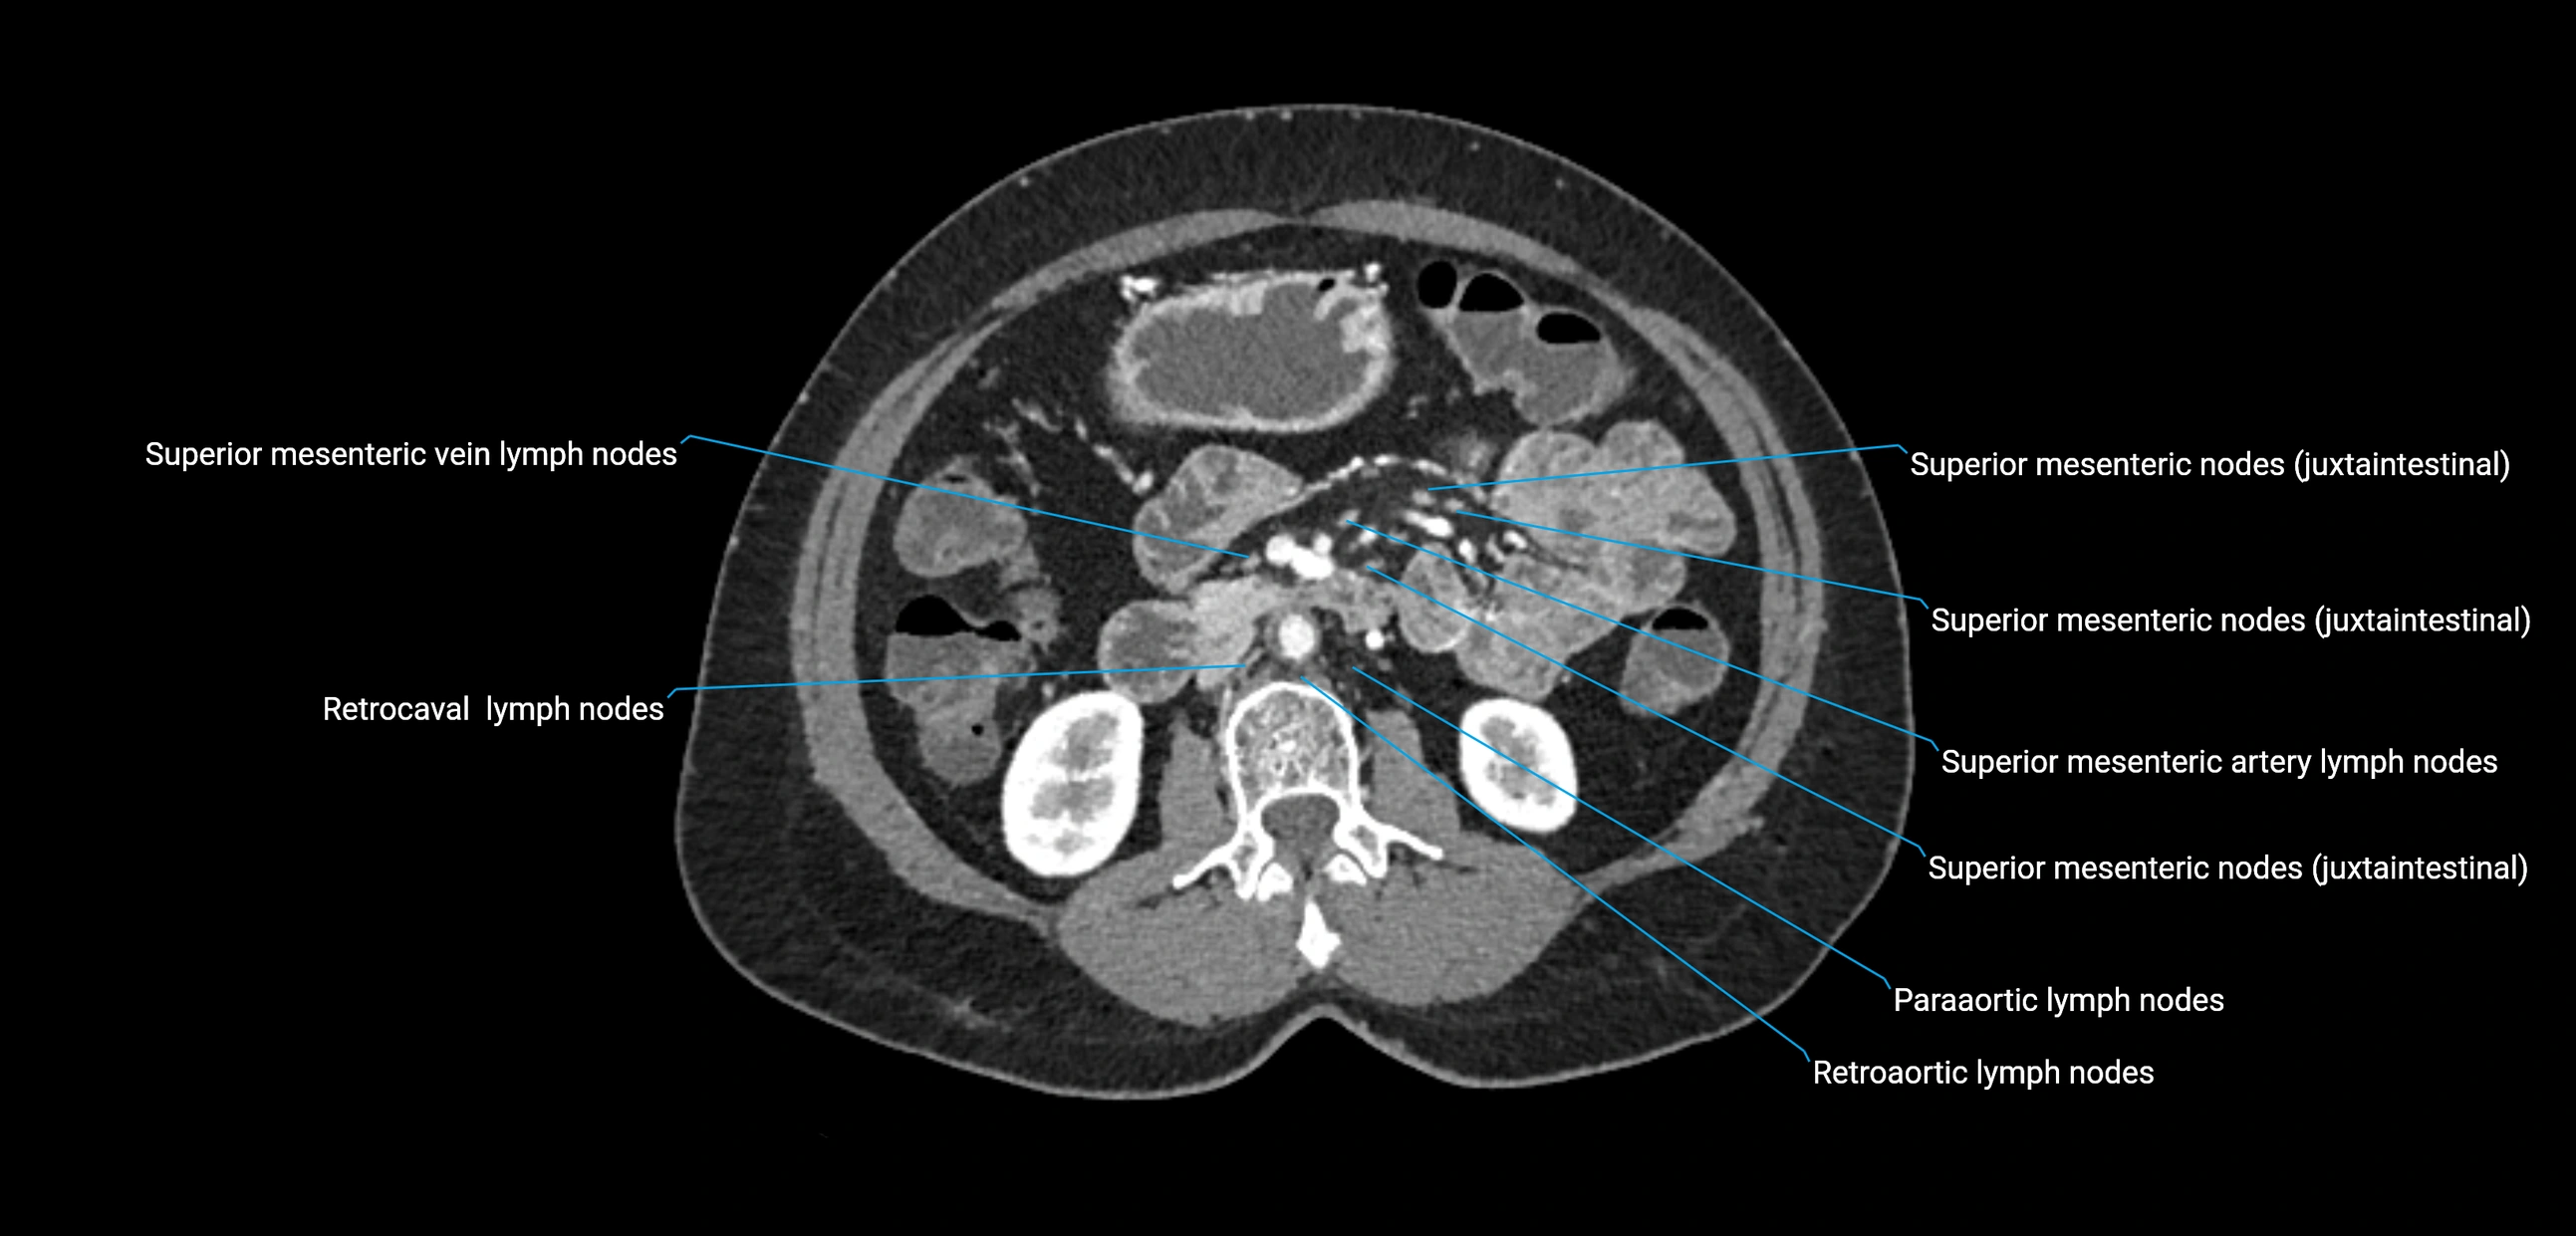

CT Appearance

CT Pre-Contrast:

• Nodes appear as soft-tissue density nodules adjacent to the aorta and IVC

• Calcification may be seen in chronic infections (e.g., tuberculosis)

CT Post-Contrast:

• Normal nodes enhance homogeneously

• Malignant nodes may show heterogeneous enhancement, central necrosis, or conglomerate formation

• Size >1 cm short axis is suspicious, though morphology and distribution are equally important

CT Venography (CTV):

• Demonstrates nodal encasement or compression of adjacent vessels (aorta, IVC, renal veins)

• Useful in staging testicular and ovarian malignancies

• Provides 3D reconstructions for retroperitoneal lymph node dissection planning

CT image

image